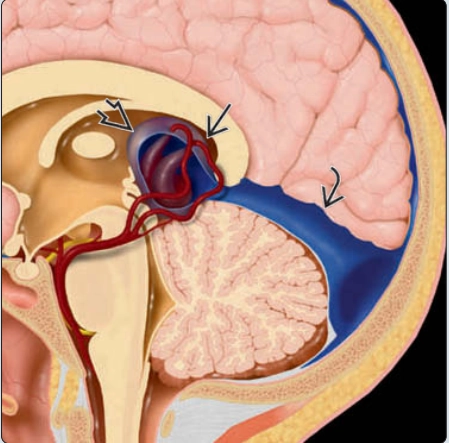

Dị dạng Dandy-Walker ở thai (Classic Dandy-Walker malformation)